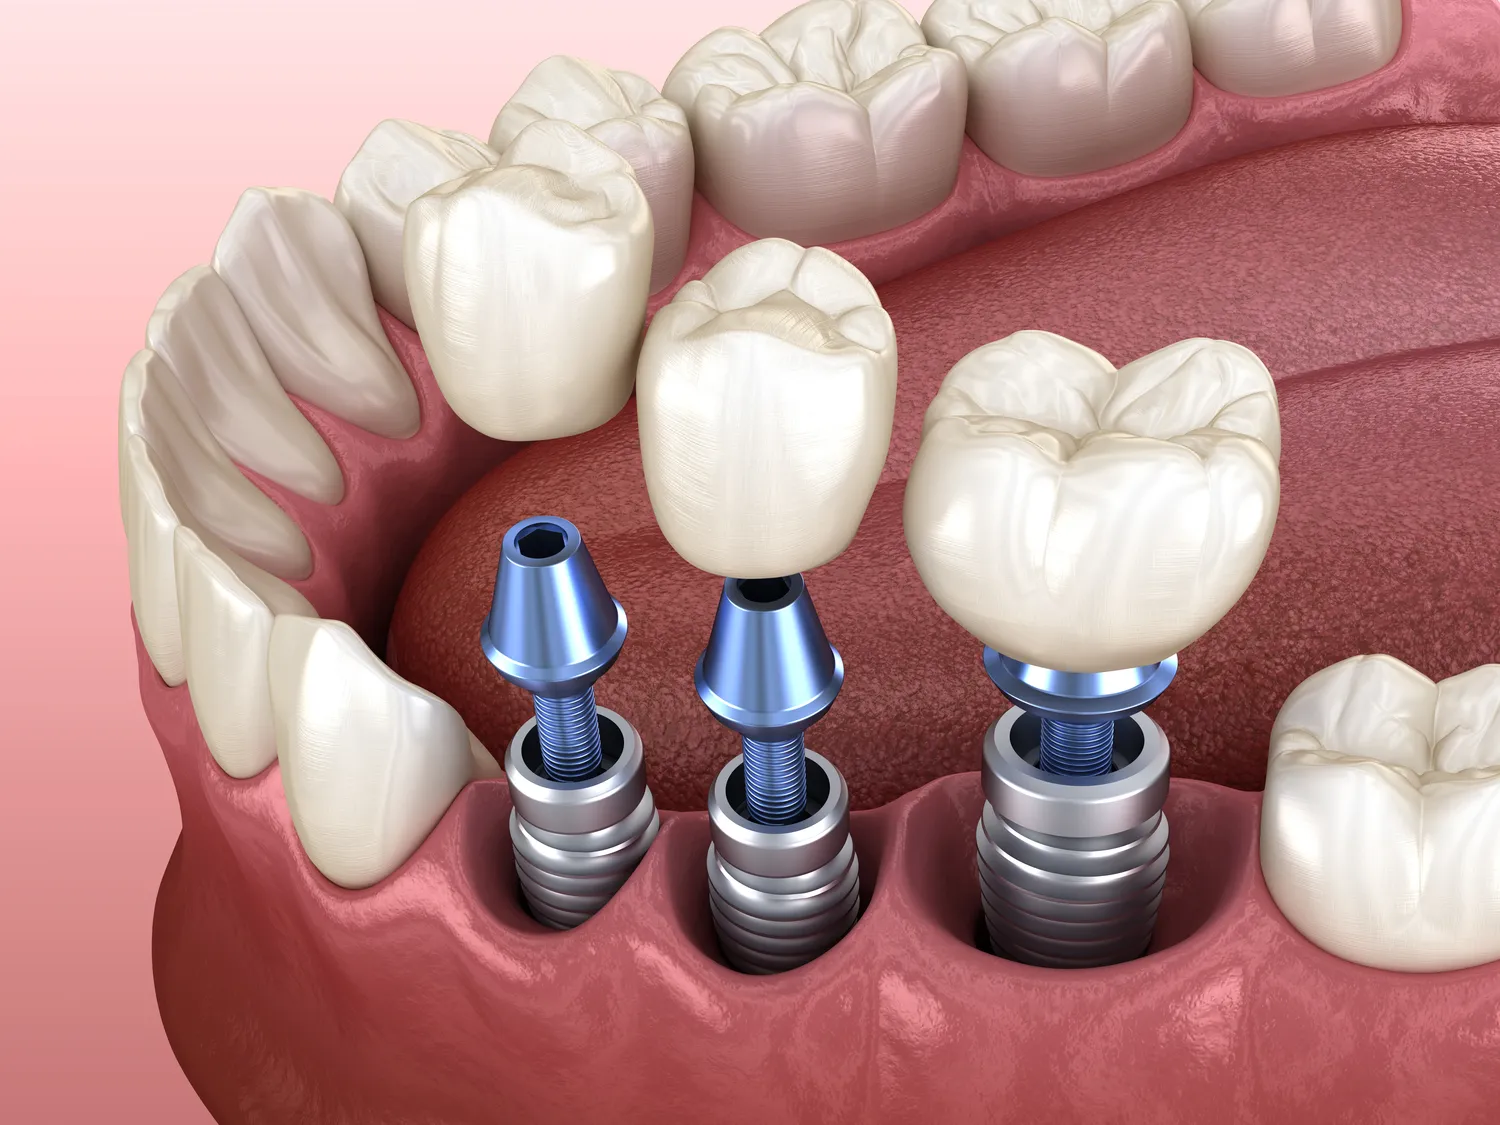

Procedura chirurgicznego wszczepienia implantu zębowego, choć może budzić obawy, jest zazwyczaj przeprowadzana w znieczuleniu miejscowym i jest dla pacjenta komfortowa. Po dokładnym zdezynfekowaniu jamy ustnej i podaniu znieczulenia, chirurg wykonuje niewielkie nacięcie w dziąśle, aby odsłonić kość. Następnie, przy użyciu specjalistycznych wierteł o stopniowo zwiększającej się średnicy, przygotowuje w kości otwór o precyzyjnie określonych wymiarach, dopasowanych do rozmiaru planowanego implantu. Kluczowe jest, aby ten proces przebiegał z odpowiednim chłodzeniem, aby uniknąć przegrzania kości, co mogłoby negatywnie wpłynąć na proces gojenia.

Gdy otwór jest gotowy, implant, który jest zazwyczaj wykonany z tytanu, jest delikatnie wkręcany lub wciskany w przygotowane łoże w kości. Implant powinien być stabilnie osadzony, co jest kluczowe dla jego późniejszej integracji z tkanką kostną. Po umieszczeniu implantu, na jego wierzchu często montuje się śrubę zamykającą lub tymczasową nakładkę, która jest następnie przykrywana przez dziąsło. W ten sposób implant pozostaje całkowicie zagłębiony w kości podczas procesu gojenia, który trwa zazwyczaj od kilku do kilkunastu tygodni. Cały zabieg, w zależności od liczby implantów i indywidualnych warunków, może trwać od kilkudziesięciu minut do kilku godzin. Po zabiegu pacjent otrzymuje zalecenia dotyczące higieny jamy ustnej, diety oraz stosowania leków przeciwbólowych i antybiotyków, jeśli zostały przepisane.

Po pomyślnym zakończeniu procesu osseointegracji, gdy implant jest już stabilnie zintegrowany z kością, rozpoczyna się etap odbudowy protetycznej. Jest to moment, w którym na implancie osadzana jest korona, która odtwarza kształt, kolor i funkcję utraconego zęba. Pierwszym krokiem jest zazwyczaj odsłonięcie implantu. Jeśli podczas pierwszej fazy chirurgicznej implant został całkowicie przykryty dziąsłem, chirurg wykonuje niewielkie nacięcie, aby uzyskać dostęp do jego powierzchni. Następnie na implancie umieszczana jest tzw. śruba gojąca. Jej zadanie polega na uformowaniu dziąsła wokół przyszłego miejsca osadzenia korony, nadając mu naturalny kształt i estetykę.

Po kilku tygodniach noszenia śruby gojącej, następuje kolejny etap, czyli pobranie wycisków. Są one niezbędne do wykonania precyzyjnej korony protetycznej w laboratorium protetycznym. W nowoczesnej stomatologii coraz częściej stosuje się skanery wewnątrzustne, które pozwalają na cyfrowe zeskanowanie jamy ustnej pacjenta i przesłanie danych do laboratorium w formie elektronicznej. Na podstawie wycisków lub skanów, technik protetyczny wykonuje koronę zębową, dopasowując jej kolor, kształt i wielkość do pozostałych zębów pacjenta. Korony te mogą być wykonane z różnych materiałów, najczęściej z ceramiki pełnoceramicznej lub porcelany na podbudowie z tlenku cyrkonu, które zapewniają doskonałą estetykę i wytrzymałość. Ostatnim etapem jest zamocowanie gotowej korony na implancie, zazwyczaj za pomocą specjalnego cementu protetycznego lub przykręcenia przez niewielki otwór w koronie.